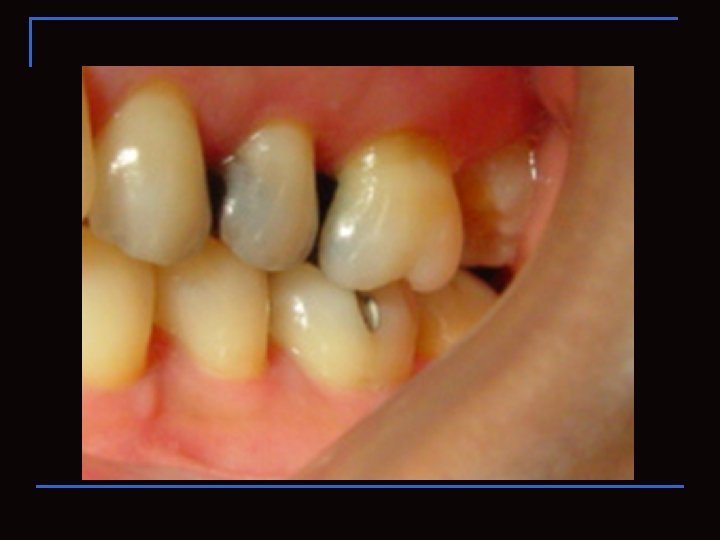

Región Vestibular